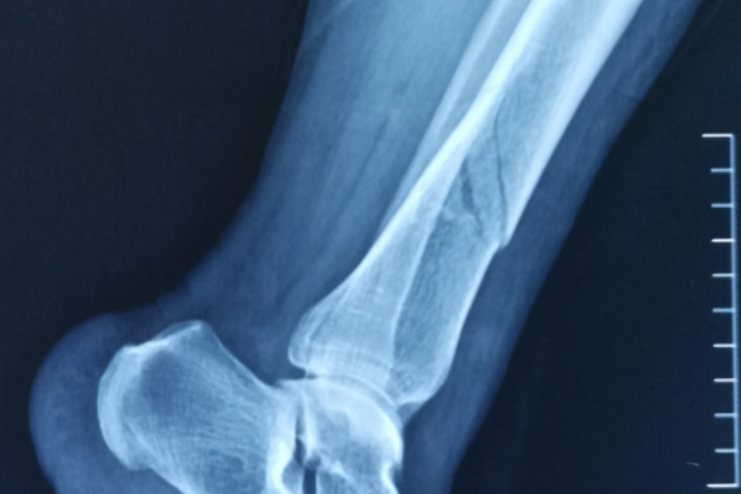

X光片是骨折在临床诊断上的重要影像学工具,常常作为首选。通过X光片不仅可以明确骨折的具体位置、类型以及骨折移位情况,帮助确定后续的治疗方案,而且价格较低,减少患者看病负担。X光片可以看见黑色透亮的骨折线,可以帮助判断患者愈合情况,常常作为复查手段。